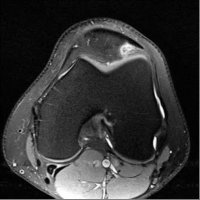

Patellar tendon-lateral femoral condyle friction syndrome, also known as Hoffa fat pad impingement syndrome, is a common cause of anterior knee pain in active individuals. It is thought to be due to patella maltracking or imbalance of the forces between medial and lateral vastus muscles causing impingement of the superolateral aspect of Hoffa fat pad between the inferior patella and the lateral femoral condyle.

Patients with Hoffa syndrome would present with acute or chronic sharp pain below the patella which is worsened by activities like walking, prolonged standing, wearing high heel shoes or any other activity that puts the knee into full extension. On examination, there may be swelling in the infrapatellar region, with point tenderness at the inferior pole of the patella.

The diagnosis is classically made with MRI and usually occult on radiography and CT. MRI findings include focal area of high T2 signal (edema) at the inferolateral aspect of the patellofemoral joint, within the superolateral portion of the infrapatellar fat pad. A cystic lesion can sometimes be found between the lateral femoral condyle and the lateral retinaculum. Associated findings include lateral patellar subluxation and patella alta (Insall-Salvati ratio greater than 1.2) which are found in around 90% of cases. Conservative treatment is usually successful, although full recovery may take time.